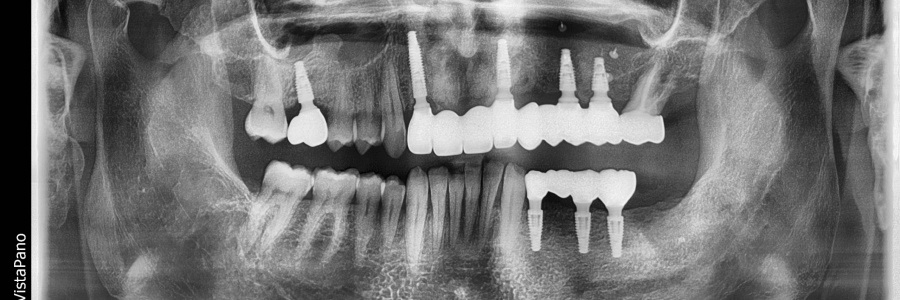

Redarea funcției masticatorii și estetice prin restaurări complexe cu ajutorul coroanelor pe implanturi tip FP1, cu aspect natural si sănătos al gingiei.

Boală parodontală tratată cu menținerea unor dinți și înlocuirea celor irecuperabili cu implanturi.

Pierderea dinților cu deficit osos considerabil, rezolvat prin tratament multidisciplinar, intervenții chirurgicale de adiție osoasă, implanturi dentare, grefe gingivale, tratament ortodontic si protetic pentru redarea zâmbetului si a funcției masticatorii

Cu ajutorul investigației CBCT și scanării intraorale, simulăm poziția exactă a implanturilor înainte de intervenție. Astfel, inserarea este precisă și predictibilă.